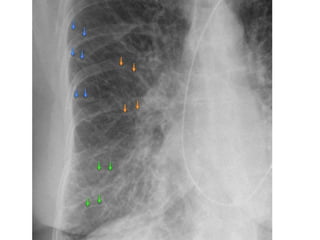

Engrosamiento vasos pulmonares